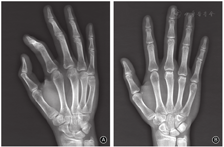

男,14岁,学生,右侧优势利手,既往体健、无风湿免疫性疾病及激素类药物使用史。5个月前因拳击伤致右手小指疼痛、肿胀、活动受限于当地就诊,余指无明显异常。X线检查提示右手小指掌骨颈骨折,断端无明显成角和移位(图1A)。予以石膏外固定保守治疗1个月,拆除石膏后开始右手功能锻炼,恢复良好。1个月前开始无明显诱因出现右手中指、环指掌指关节疼痛,活动时加重,手指不能伸直,右手抓握力降低,未行特殊治疗,症状逐渐加重后来我院就诊。

右手X线片示第5掌骨骨折愈合,第3、4掌骨头关节面变平,局部骨小梁中断、低密度透光区,软骨下塌陷、局部骨质硬化,无明显的掌指关节半脱位(图1B)。CT片示右手第3、4掌骨头坏死,背侧见囊状低密度灶、周围局部骨质硬化,关节面皮质骨缺损(图2)。实验室检查:血常规、红细胞沉降率、IL-6、类风湿因子等血清学检查指标正常。诊断为右手第3、4掌骨头缺血性坏死。